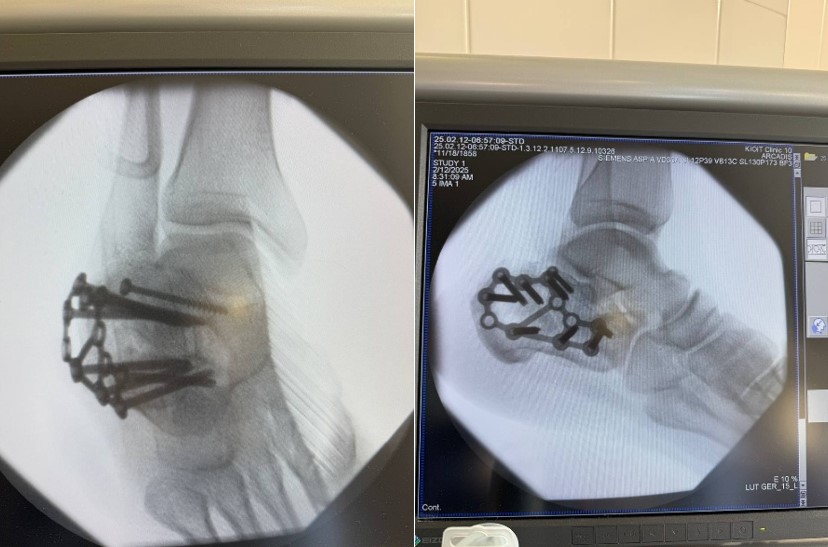

Відкрита репозиція та внутрішня фіксація за допомогою МОС — так красиво звучить назва того, що насправді є тривалою, кропіткою битвою за кожен міліметр. Хірург збирає уламки, один за одним, повертає на місце, відновлює суглобову поверхню — вона має стати гладкою, як дзеркало, інакше майбутнє буде наповнене болем та артрозом.

Спеціальні пластини та гвинти — це арматура, що тримає відновлену конструкцію. Вони вживлюються у кістку, стають її частиною, екзо- та ендо- скелетом всередині кальцієвого. Це технологія та мистецтво одночасно. Операція може тривати години, кожен шматок має стати на своє місце, кожен гвинт вкручений під правильним кутом, щоб не заподіяти шкоди вже пошкодженим тканинам.